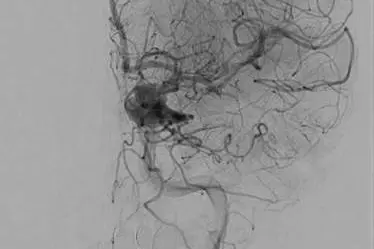

Den avanserte metoden utføres av spesialiserte røntgenleger. De fører et kateter inn i pulsåren i lysken, opp gjennom hovedpulsåren og inn i hjernen. I enden har de et nett, der blodproppen fester seg før den trekkes ut igjen.

Kontrastvæske gjør det mulig å se hvor blodproppen befinner seg.

Bildet er tatt fra en øvelse med simuleringsdukke. Teamet øver hver 14. dag.